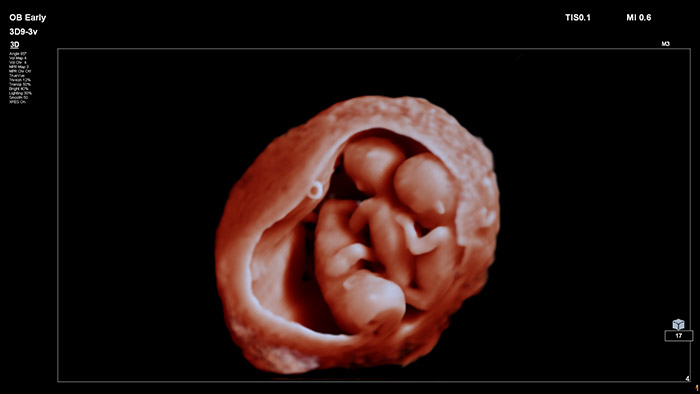

En este vídeo, el Dr. Michael Ruma presenta el transductor V9-2 para ultrasonidos 3D de Philips. El V9-2 es el primer transductor mecánico PureWave para ultrasonidos 3D de la división de ultrasonidos de Philips específico para obstetricia/ginecología y ofrece una extraordinaria calidad de imagen y un diseño ergonómico avanzado. El V9-2 está especialmente indicado para la adquisición de imágenes 2D, 3D y 4D para exploraciones obstétricas del primer, segundo y tercer trimestre.

Combinar el nuevo transductor V9-2 con el sistema de ultrasonidos de alta gama EPIQ Elite ofrece una adquisición de imágenes superior de obstetricia/ginecología:

Herramientas de visualización obstétrica avanzadas para una imagen fetal realista.